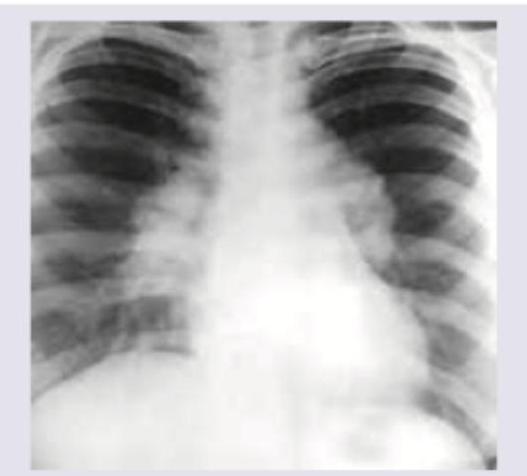

Question 10: A 35-year-old woman presents with breathlessness at rest. She also complains of a skin lesion on nose which has increased in size for last 6 months. What is the diagnosis?

- A. Sarcoidosis (Correct Answer)

- B. Phakomatosis

- C. Pulmonary lymphagiomatosis

- D. DRESS syndrome

Explanation: ***Sarcoidosis*** - Sarcoidosis is a multisystem **granulomatous disease** that commonly involves the lungs (causing **breathlessness**) and skin (manifesting as **lesions on the nose**, such as lupus pernio). The chest X-ray likely shows lung involvement like **bilateral hilar lymphadenopathy** or interstitial infiltrates. - The combination of **pulmonary symptoms** and characteristic **skin lesions** in a young to middle-aged adult is highly suggestive of sarcoidosis. *Phakomatosis* - Phakomatoses are a group of syndromes characterized by tumors or malformations of the skin, nervous system, and sometimes other organs. - While they can have skin lesions (e.g., neurofibromas, angiomas) and sometimes central nervous system or visceral involvement, **breathlessness is not a primary or typical presenting symptom**, and their CXR findings are usually normal unless there is specific lung involvement not characteristic of sarcoidosis. *Pulmonary lymphangiomatosis* - Pulmonary lymphangiomatosis is a rare, benign disease involving the proliferation of **lymphatic vessels** within the lung parenchyma, mediastinum, and pleura. - While it can cause breathlessness, **skin lesions on the nose are not a feature** of this condition, making it an unlikely diagnosis in this clinical context. *DRESS syndrome* - **DRESS (Drug Rash with Eosinophilia and Systemic Symptoms) syndrome** is a severe adverse drug reaction characterized by a widespread skin rash, fever, eosinophilia, and internal organ involvement (e.g., liver, kidneys). - While it presents with a skin lesion and systemic symptoms, the **onset is usually acute** following drug exposure, and the skin lesion on the nose described as increasing in size over 6 months is not typical for DRESS. Additionally, the pulmonary involvement differs from granulomatous disease.